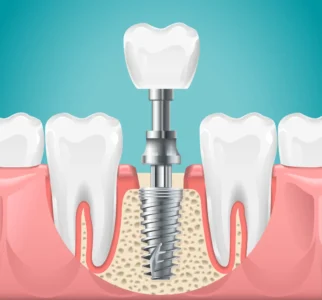

ایمپلنت دندان، یکی از مطمئنترین و مدرنترین روشها برای جایگزینی دندانهای ازدسترفته است. اما برای اینکه این سرمایهگذاری برای شما موفقیتآمیز باشد و ایمپلنتتان برای سالها بدون هیچ مشکلی کار کند، رعایت مراقبتهای بعد از ایمپلنت دندان حیاتی است. این مراقبتها به اندازه مهارت جراح اهمیت دارند و موفقیت نهایی درمان را تضمین میکنند.

در این دوره، فرآیند مهم جوش خوردن ایمپلنت با استخوان (Osseointegration) در حال انجام است. وارد کردن فشار زیاد میتواند این فرآیند را مختل کند.